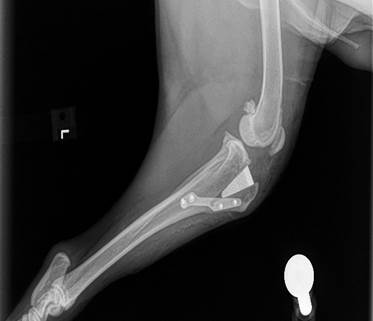

Tibial Tuberosity Advancement (TTA)

This procedure is used to treat cruciate ligament tears by stabilizing the knee joint and altering the forces acting on it. It’s typically recommended for select dogs with specific knee structure and activity levels.